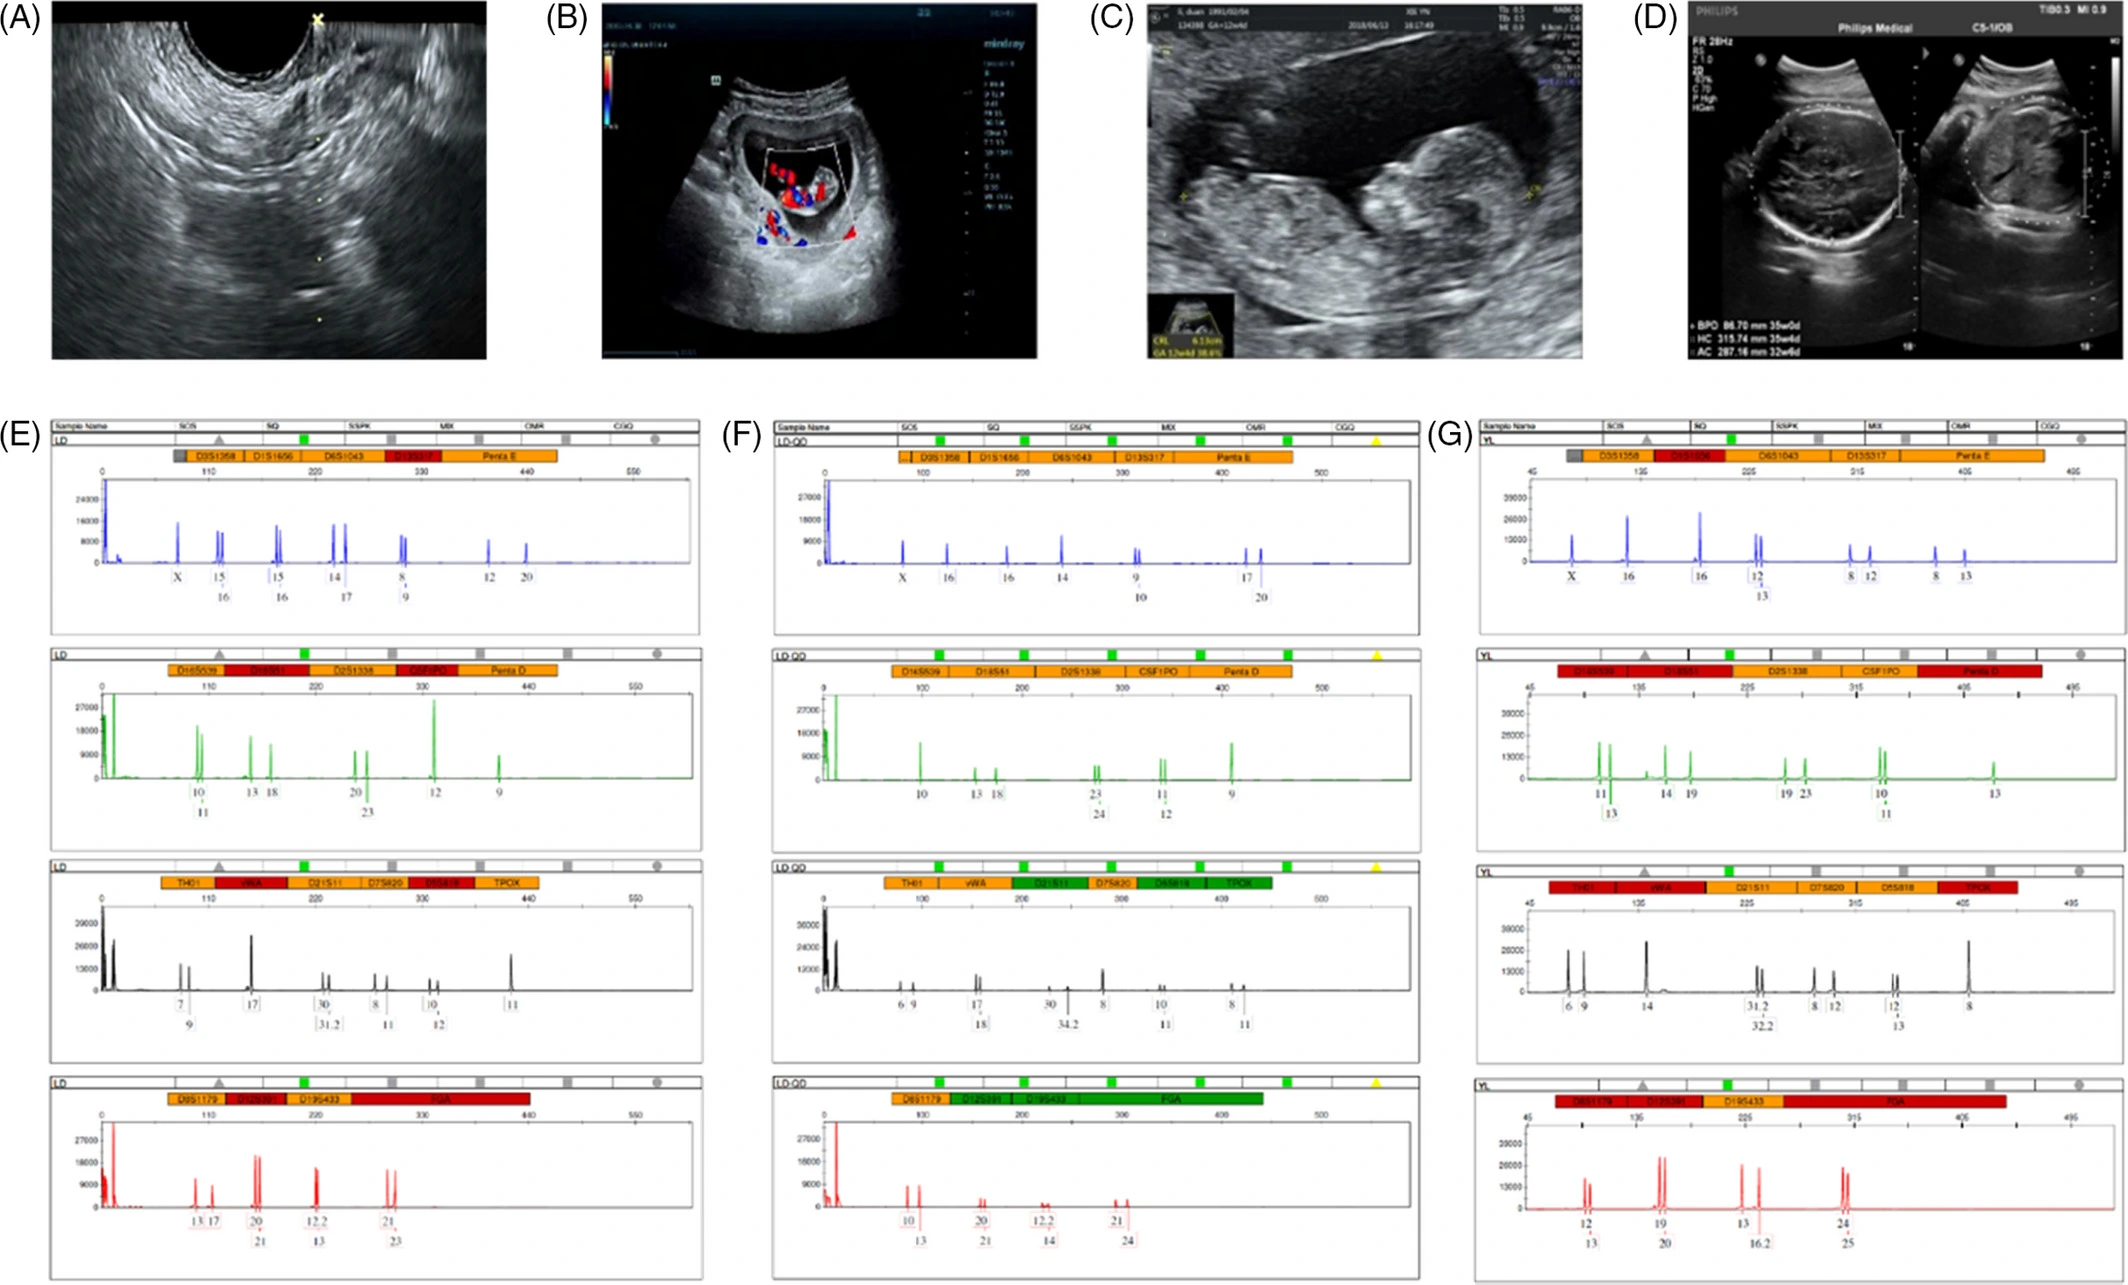

方法:本研究共纳入61例确诊为POI的患者,按照GMP标准分离培养UCMSCs,在阴道超声引导下原位注射至患者卵巢,随访期间监测副作用、生命体征及临床变化,并收集血液学及影像学参数。(见图1)

结果显示:4例胎儿分娩时没有出生缺陷,其中1例为自然受孕,其余3例来自ICSI受精类型。一位患者在接受体外受精后成功妊娠,产前检查超声扫描显示胎儿发育正常。微卫星位点分析确认了胎儿与母亲之间的遗传关系,排除了供体UCMSC的影响。(见图3)